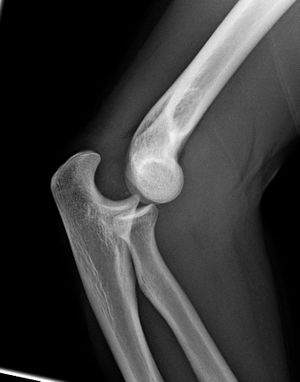

Close-up radiograph, right elbow-joint